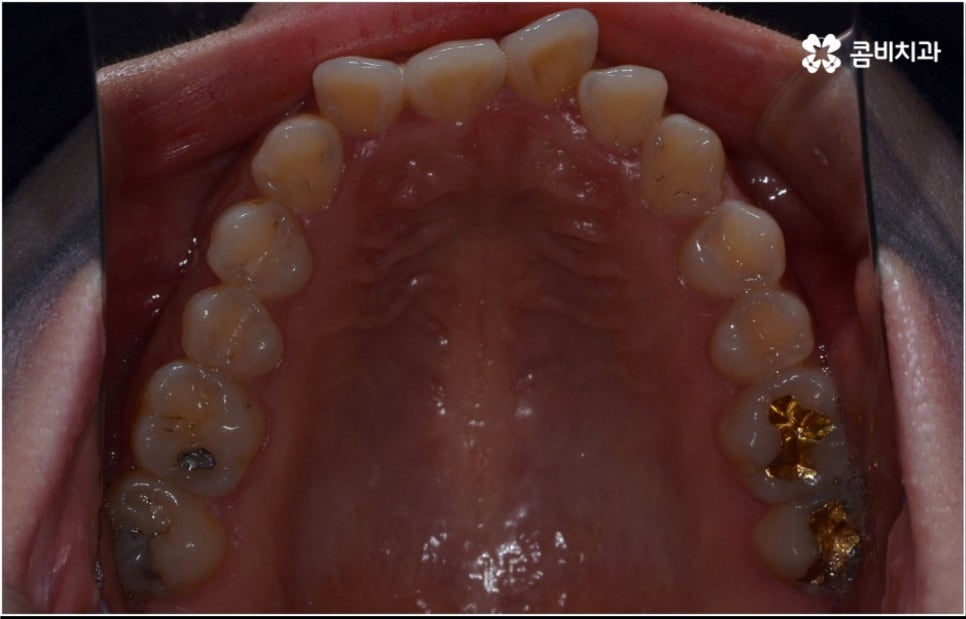

3D CT 등 정밀 검진 기계를 통해 꼼꼼하게 검진을 한 후 환자분들의 부정교합의 종류 및 정도 등에 따라 각자에게 맞는 교정 치료 계획을 수립하게 되는데, 내부 공간이 얼마나 있는지에 따라 발치가 필요한지 아닌지 여부도 달라지고 또 같은 부정교합이라고 해도 사람마다 잇몸 건강이나 치근 상태 등에 따라 잇몸뼈가 벌어지면서 치아가 이동하는 속도, 치아가 자리잡는 양상 등도 모두 달라지기 때문에 성인 치아교정 기간 총 소요 시간은 모두 달라질 수 밖에 없을 거예요.

치열이 삐뚤어져 있으면 기능적 심미적으로도 불편하지만 구강 건강과 관련하여 음식물 찌꺼기가 자주 끼고 충치 및 잇몸병과 같은 구강 질환에 노출될 가능성이 높아지는 등 관리가 어렵다는 문제도 커지기 때문에, 점점 길어지는 노년기에 건강하고 활기찬 생활을 하기 위해서 구강 건강이 굉장히 중요한 역할을 한다는 점을 상기해 봤을 때 중장년 성인 교정 치료에 대해서 괜한 두려움으로 미루기 보다는 더 늦기 전에 검진을 받아보고 필요한 도움을 받을 수 있는지 적극적으로 알아보는 것이 보다 바람직한 태도라고 할 수 있을 거예요.